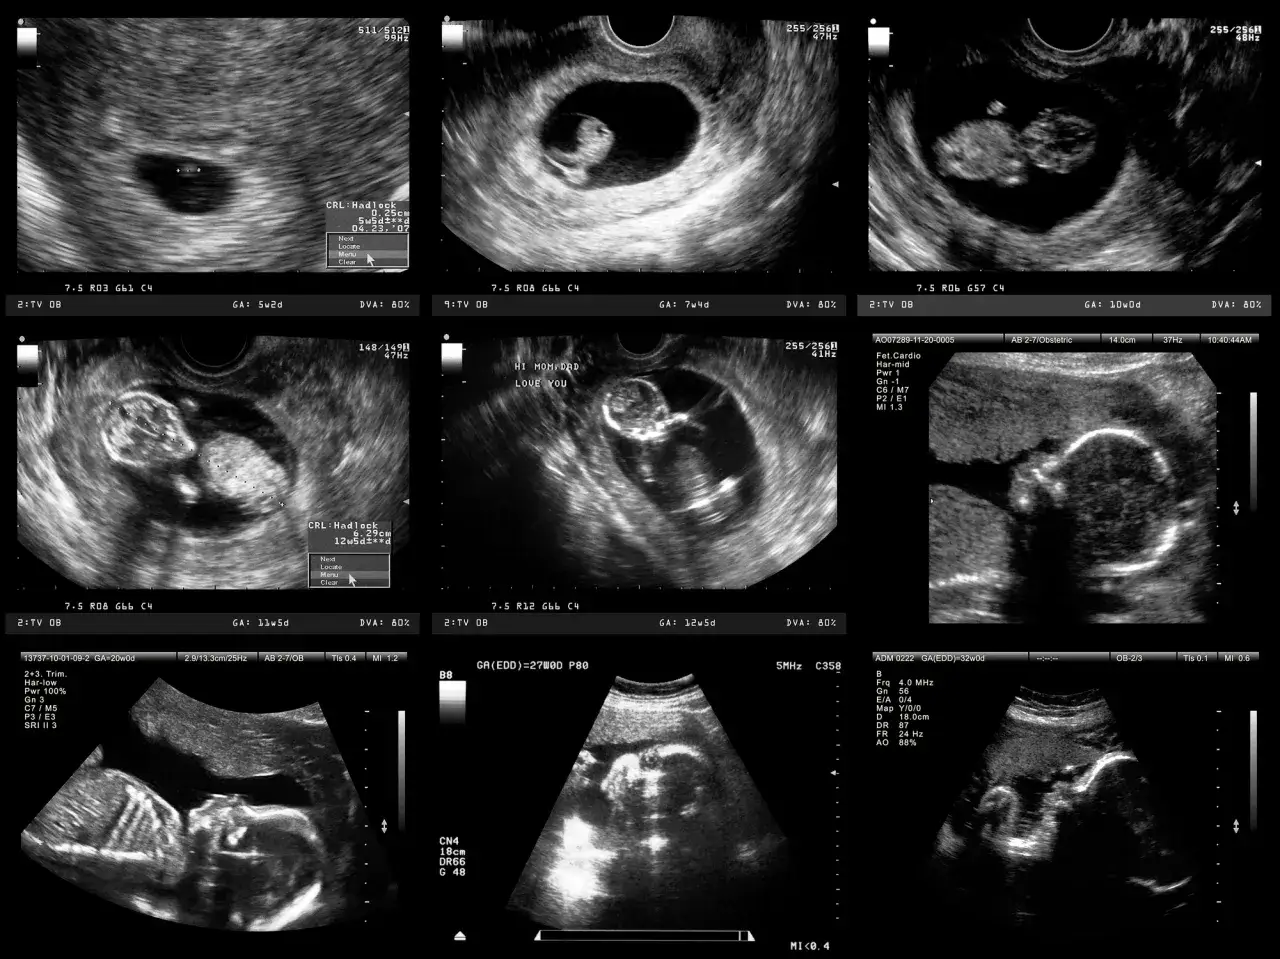

Podczas pierwszej wizyty możesz spodziewać się badania ginekologicznego, USG (aby potwierdzić ciążę w macicy i wykluczyć ciążę pozamaciczną), a także skierowania na podstawowe badania krwi i moczu, które są standardem w ciąży.

W obliczu wspomnianych ryzyk, badania prenatalne nabierają szczególnego znaczenia dla kobiet w ciąży po 40. roku życia. To właśnie dzięki nim możemy wcześnie wykryć ewentualne nieprawidłowości, monitorować rozwój dziecka i zdrowie matki. Badania takie jak USG genetyczne, testy przesiewowe (np. test PAPP-A, NIPT) czy w niektórych przypadkach diagnostyczne (amniopunkcja, biopsja kosmówki) dają nam cenne informacje. Pozwalają na wczesne reagowanie, a w wielu przypadkach na uspokojenie obaw, gdy wyniki są prawidłowe. Świadome korzystanie z dostępnych badań prenatalnych to jeden z filarów bezpiecznego i spokojnego dojrzałego macierzyństwa.